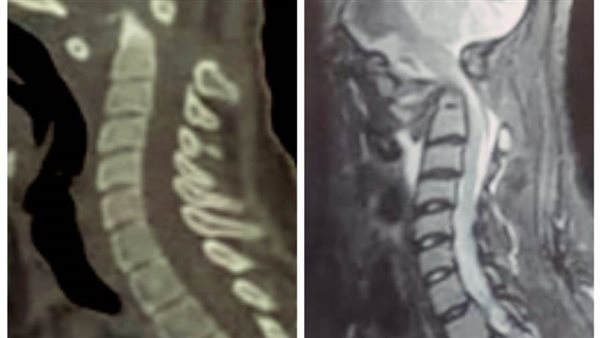

صرح رئيس جامعة سوهاج بأن قسم جراحة المخ والأعصاب بالمستشفى الجامعي نجح في إجراء تدخل جراحي نادراً ويعد الأول من نوعه فى صعيد مصر، لفتاة تبلغ من العمر ١٨ عاماً، وتعانى من مرض خلقي الانغماس القاعدي مع عدم ثبات قاع الجمجمة في الاتصال بالفقرات العنقية، وهي من الحالات النادرة الحدوث، حيث أدى هذا المرض إلى إصابة الفتاة بشلل رباعي حاد نتيجة الضغط على الحبل الشوكي وجذع المخ بقاع الجمجمة.

وقال الدكتور مجدي أمين القاضي عميد كلية الطب البشري ورئيس مجلس إدارة المستشفيات الجامعية إنه تم على الفور حجز المريضة بالقسم والتجهيز للتدخل الجراحى لتوسيع قاع الجمجمة مع استعدال الاعوجاج الفقرات العنقية وإعادتها الى الوضع التشريحي الطبيعي وتثبيتها بقاع الجمجمة.

وذكر الدكتور حمدي سعد المدير التنفيذي للمستشفيات الجامعية انه تم خروج المريضة من غرفة العمليات إلى العناية المركزة لمتابعة الوظائف الحيوية، والتي أثبتت استقرار حالتها والتحسن في الحركة على مستوى الأطراف الأربعة، وتم خروج المريضة من العناية المركزة إلى القسم الداخلي لتستطيع المشي بعد مرور شهر وهي طريحة الفراش.